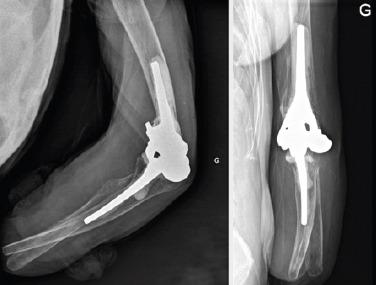

CASE REPORT

We report the case of an older spastic patient with bilateral forearm amputation for whom we performed a total elbow arthroplasty for a complex left distal humerus fracture. At 1 year follow-up, our patient was satisfied with the outcome as she had recovered her previous range motion and autonomy. There was no sign of implant loosening or migration on radiographs.

CONCLUSIONS

Given that this treatment has the same benefits as in the typical target population and that any complications that may occur could be less devastating in a patient with forearm amputation. We think that elbow arthroplasty should be offered, in case of complex articular fracture, to all older patients with forearm amputation who has functional demands.